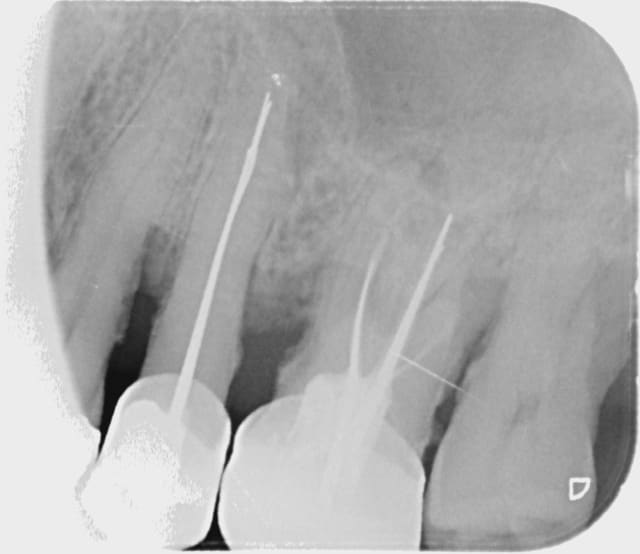

Img 1392 s73srk - Eugenol

Les cônes d'argent ont un profil "élégant" et bien radio-opaque ...))) Bin , il a un pb paro , généralisé d'ailleurs mais il veut l'ignorer et se brosse 3 fois par jour , et passe même les brossettes , ça se sent pas ...)))

All rob 014 jdqg6w - Eugenol

Il a aussi de belles lipoes.